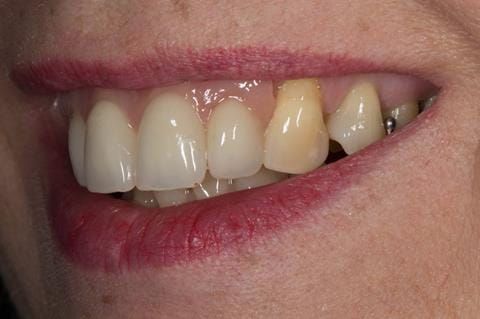

- High smile line showing gum above gingival zeniths of upper front teeth when smiling. Aesthetic failure of the upper four incisors with inflammation of the gingivae and mis-match of the gingival zenith levels.

Following consultation and second discussion appointment the patient chose to have option 3 namely, a maxillary cobalt chromium based partial denture/protective occlusal splint. The clinical situation and treatment process is shown in detail below with photographs. The patient was successfully rehabilitated with this and her quality of life considerably improved. The clinical work was provided by Finlay and the technical work by Rowan.